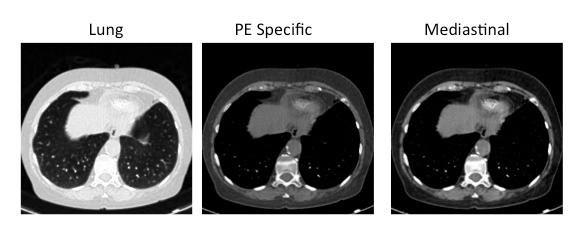

- 8-bit RGB 512 x 512 images.

- Windowing technique for these CT scans:

RED channel / LUNG window / level=-600, width=1500

GREEN channel / PE window / level=100, width=700

BLUE channel / MEDIASTINAL window / level=40, width=400